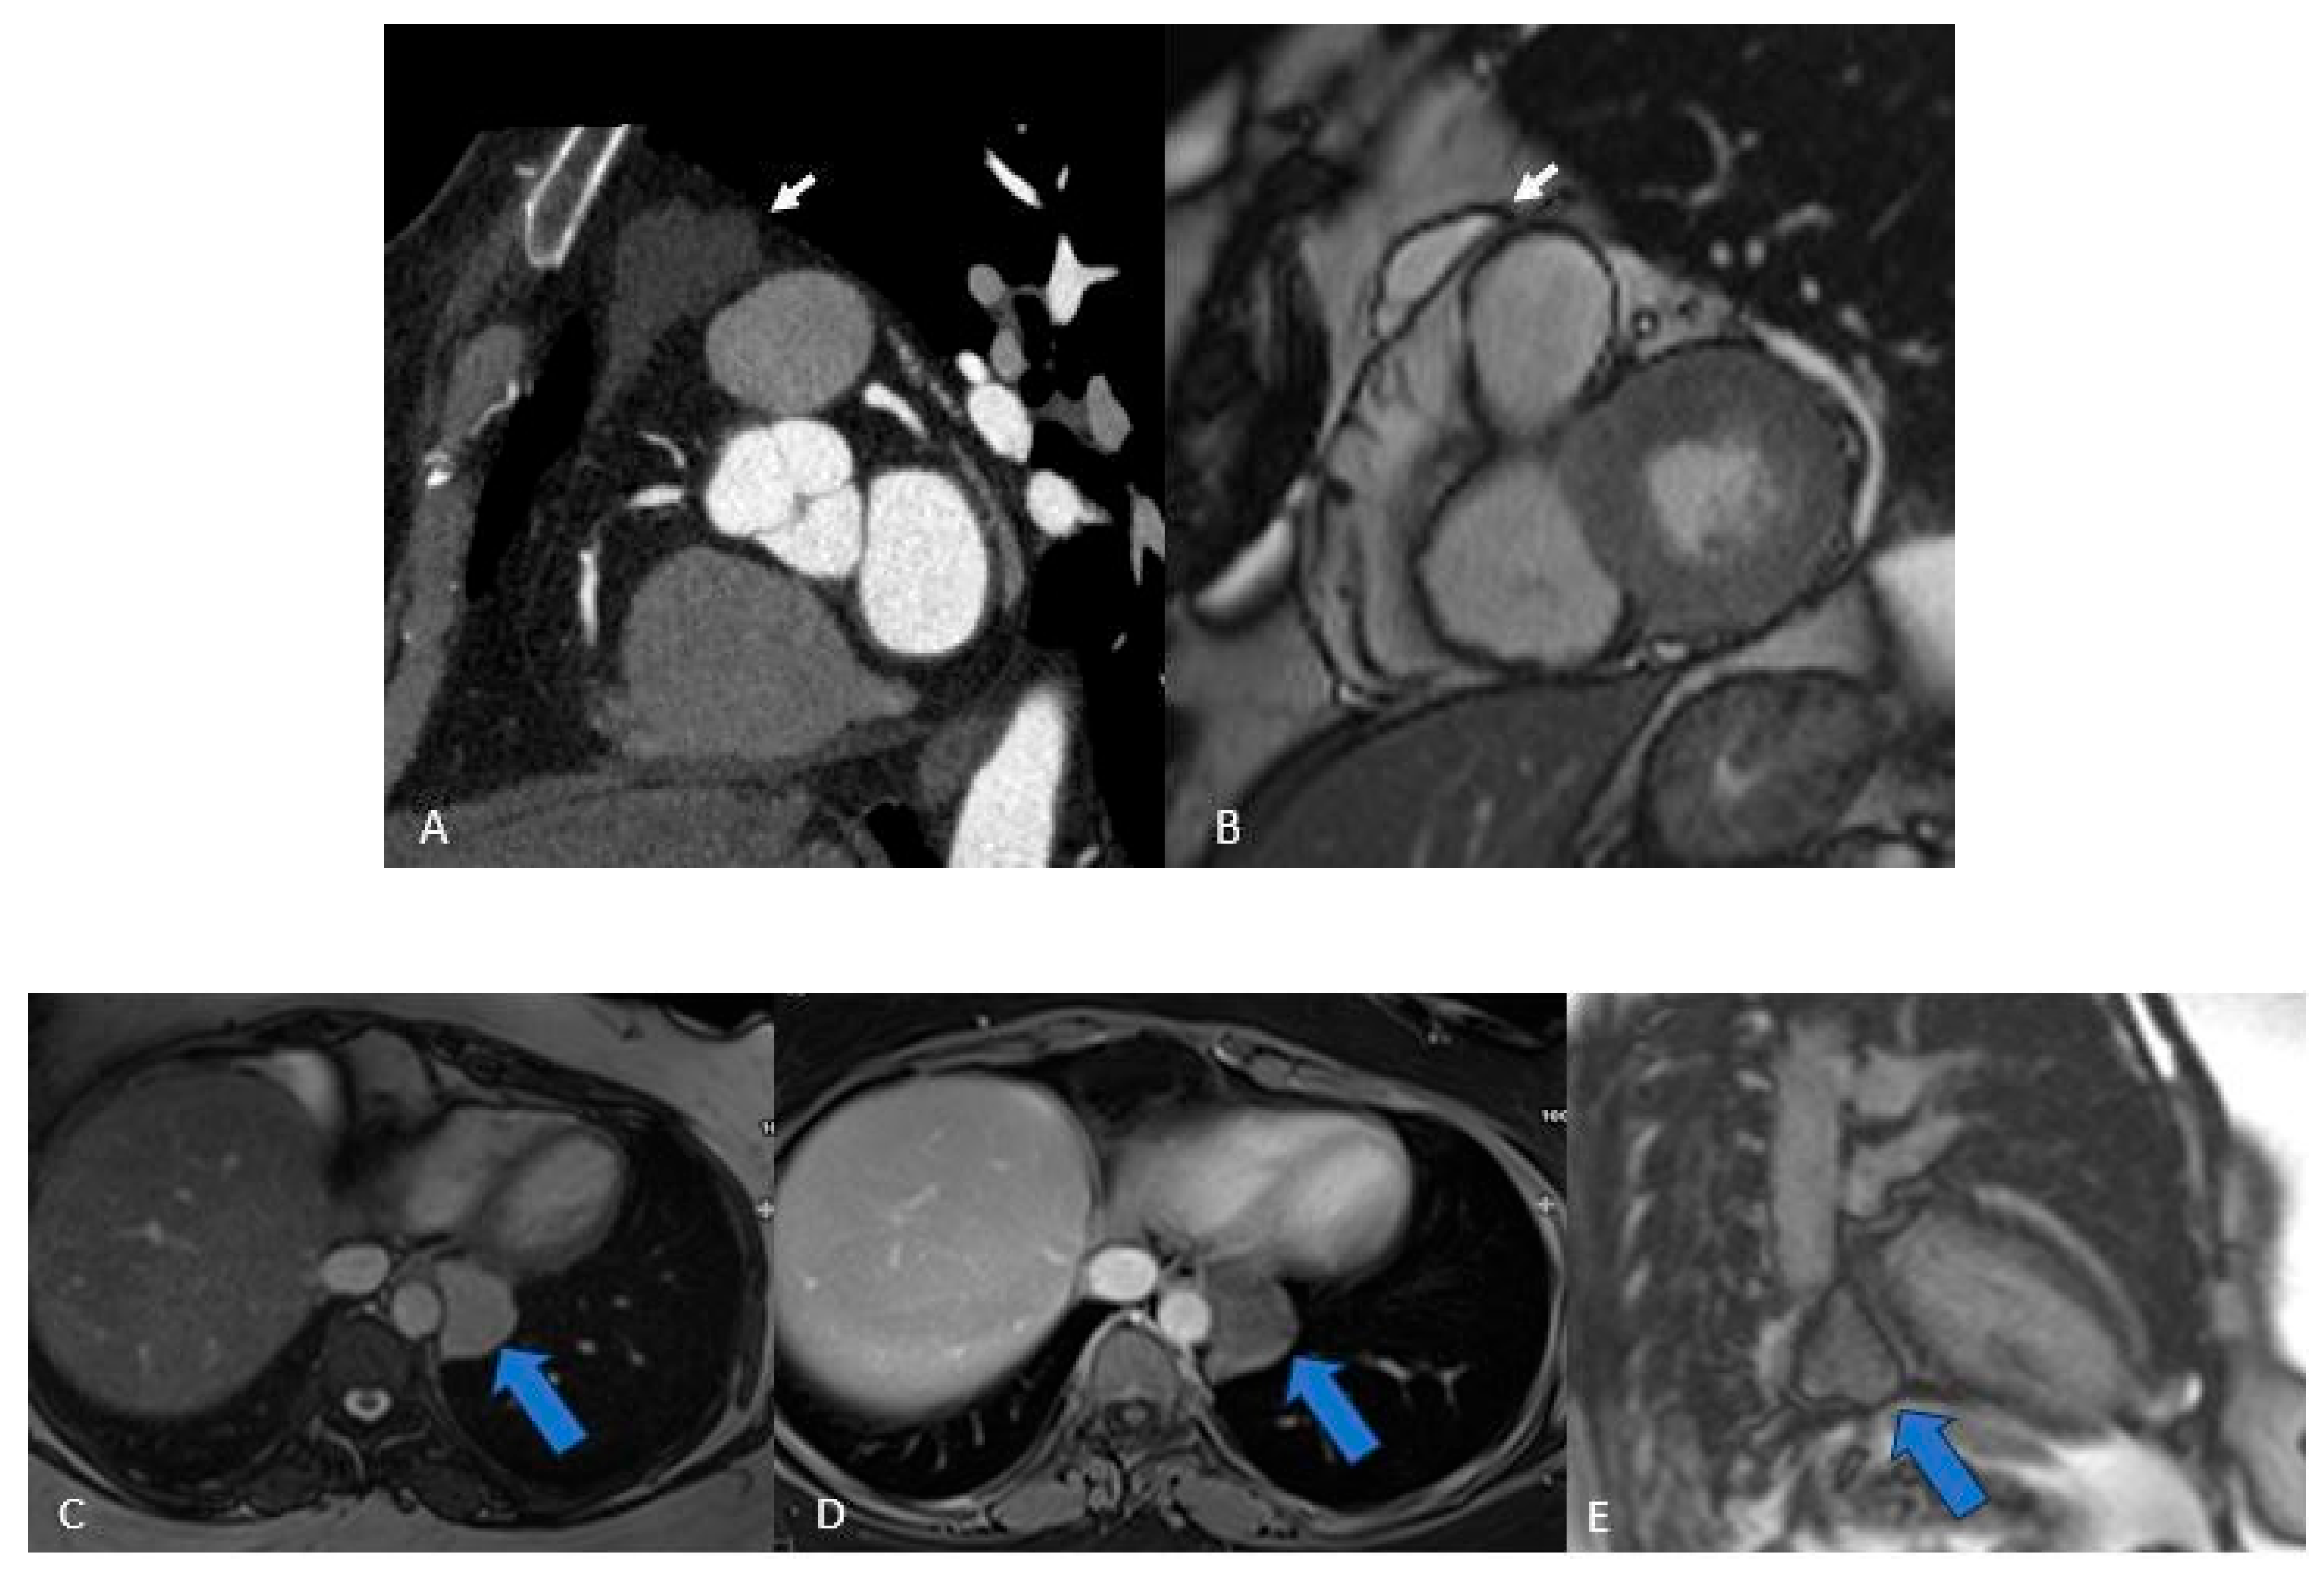

Thrombi reveal themselves as non-opacified (“vacuum”) areas after contrast injection (Figure 3)—critical to recognize for proper treatment—and are classically found in the left atrium of patients with atrial fibrillation. On CT they appear as hypodense, non-enhancing lesions [29]; on MRI their signal shifts with age: acute clots display intermediate intensity on both T1 and T2 (due to oxyhemoglobin), subacute thrombi become T1-dark and T2-bright as hemoglobin converts to methemoglobin and draws in water, and chronic, fibrosed clots lose water, appear dark on both T1 and T2, and generally lack contrast uptake (though longstanding fibrotic thrombi can show rim enhancement on delayed sequences), similar to normal fibrotic tissue [2,3,12,30].

Figure 3. Thrombus (white arrows). CINE (A), EGE (B), and LGE (C) sequences show a large thrombus (arrows) at the apex of the left ventricle. Note that it remains hypointense and does not take up contrast, which is typical of thrombi and helps in distinguishing them from other cardiac masses.